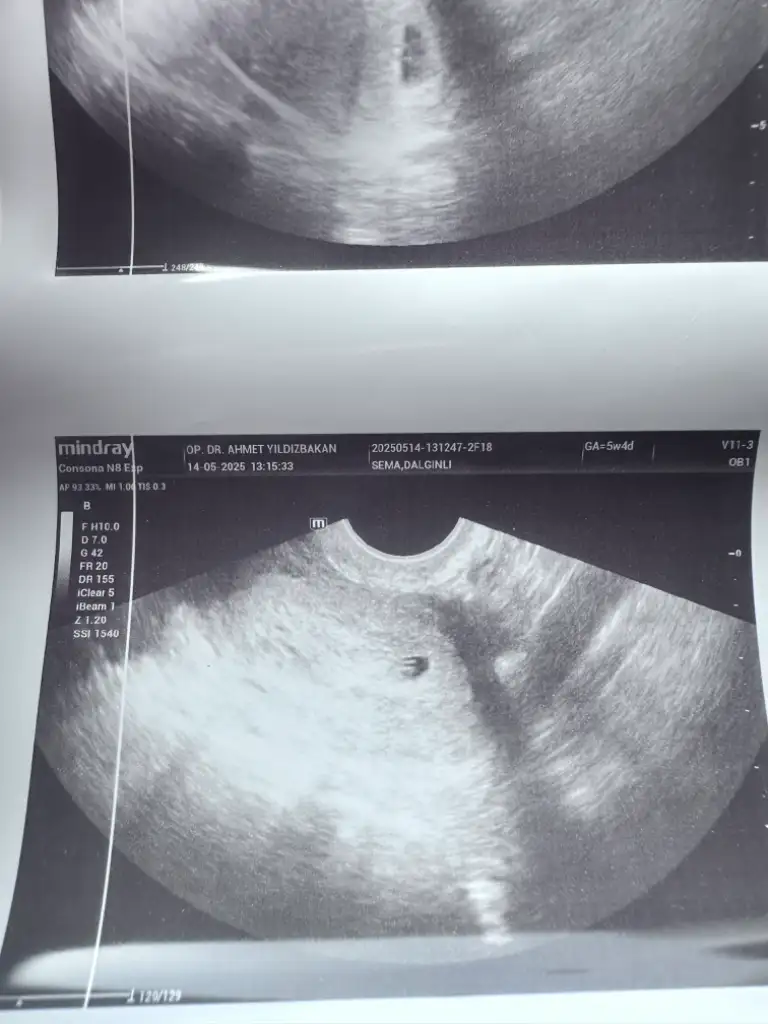

Kızlar selam keseme bakar mısınız normal mi 5+2 bugün

5+4 haftalıksın cnm ultrasyon kâğıdın öyle dior